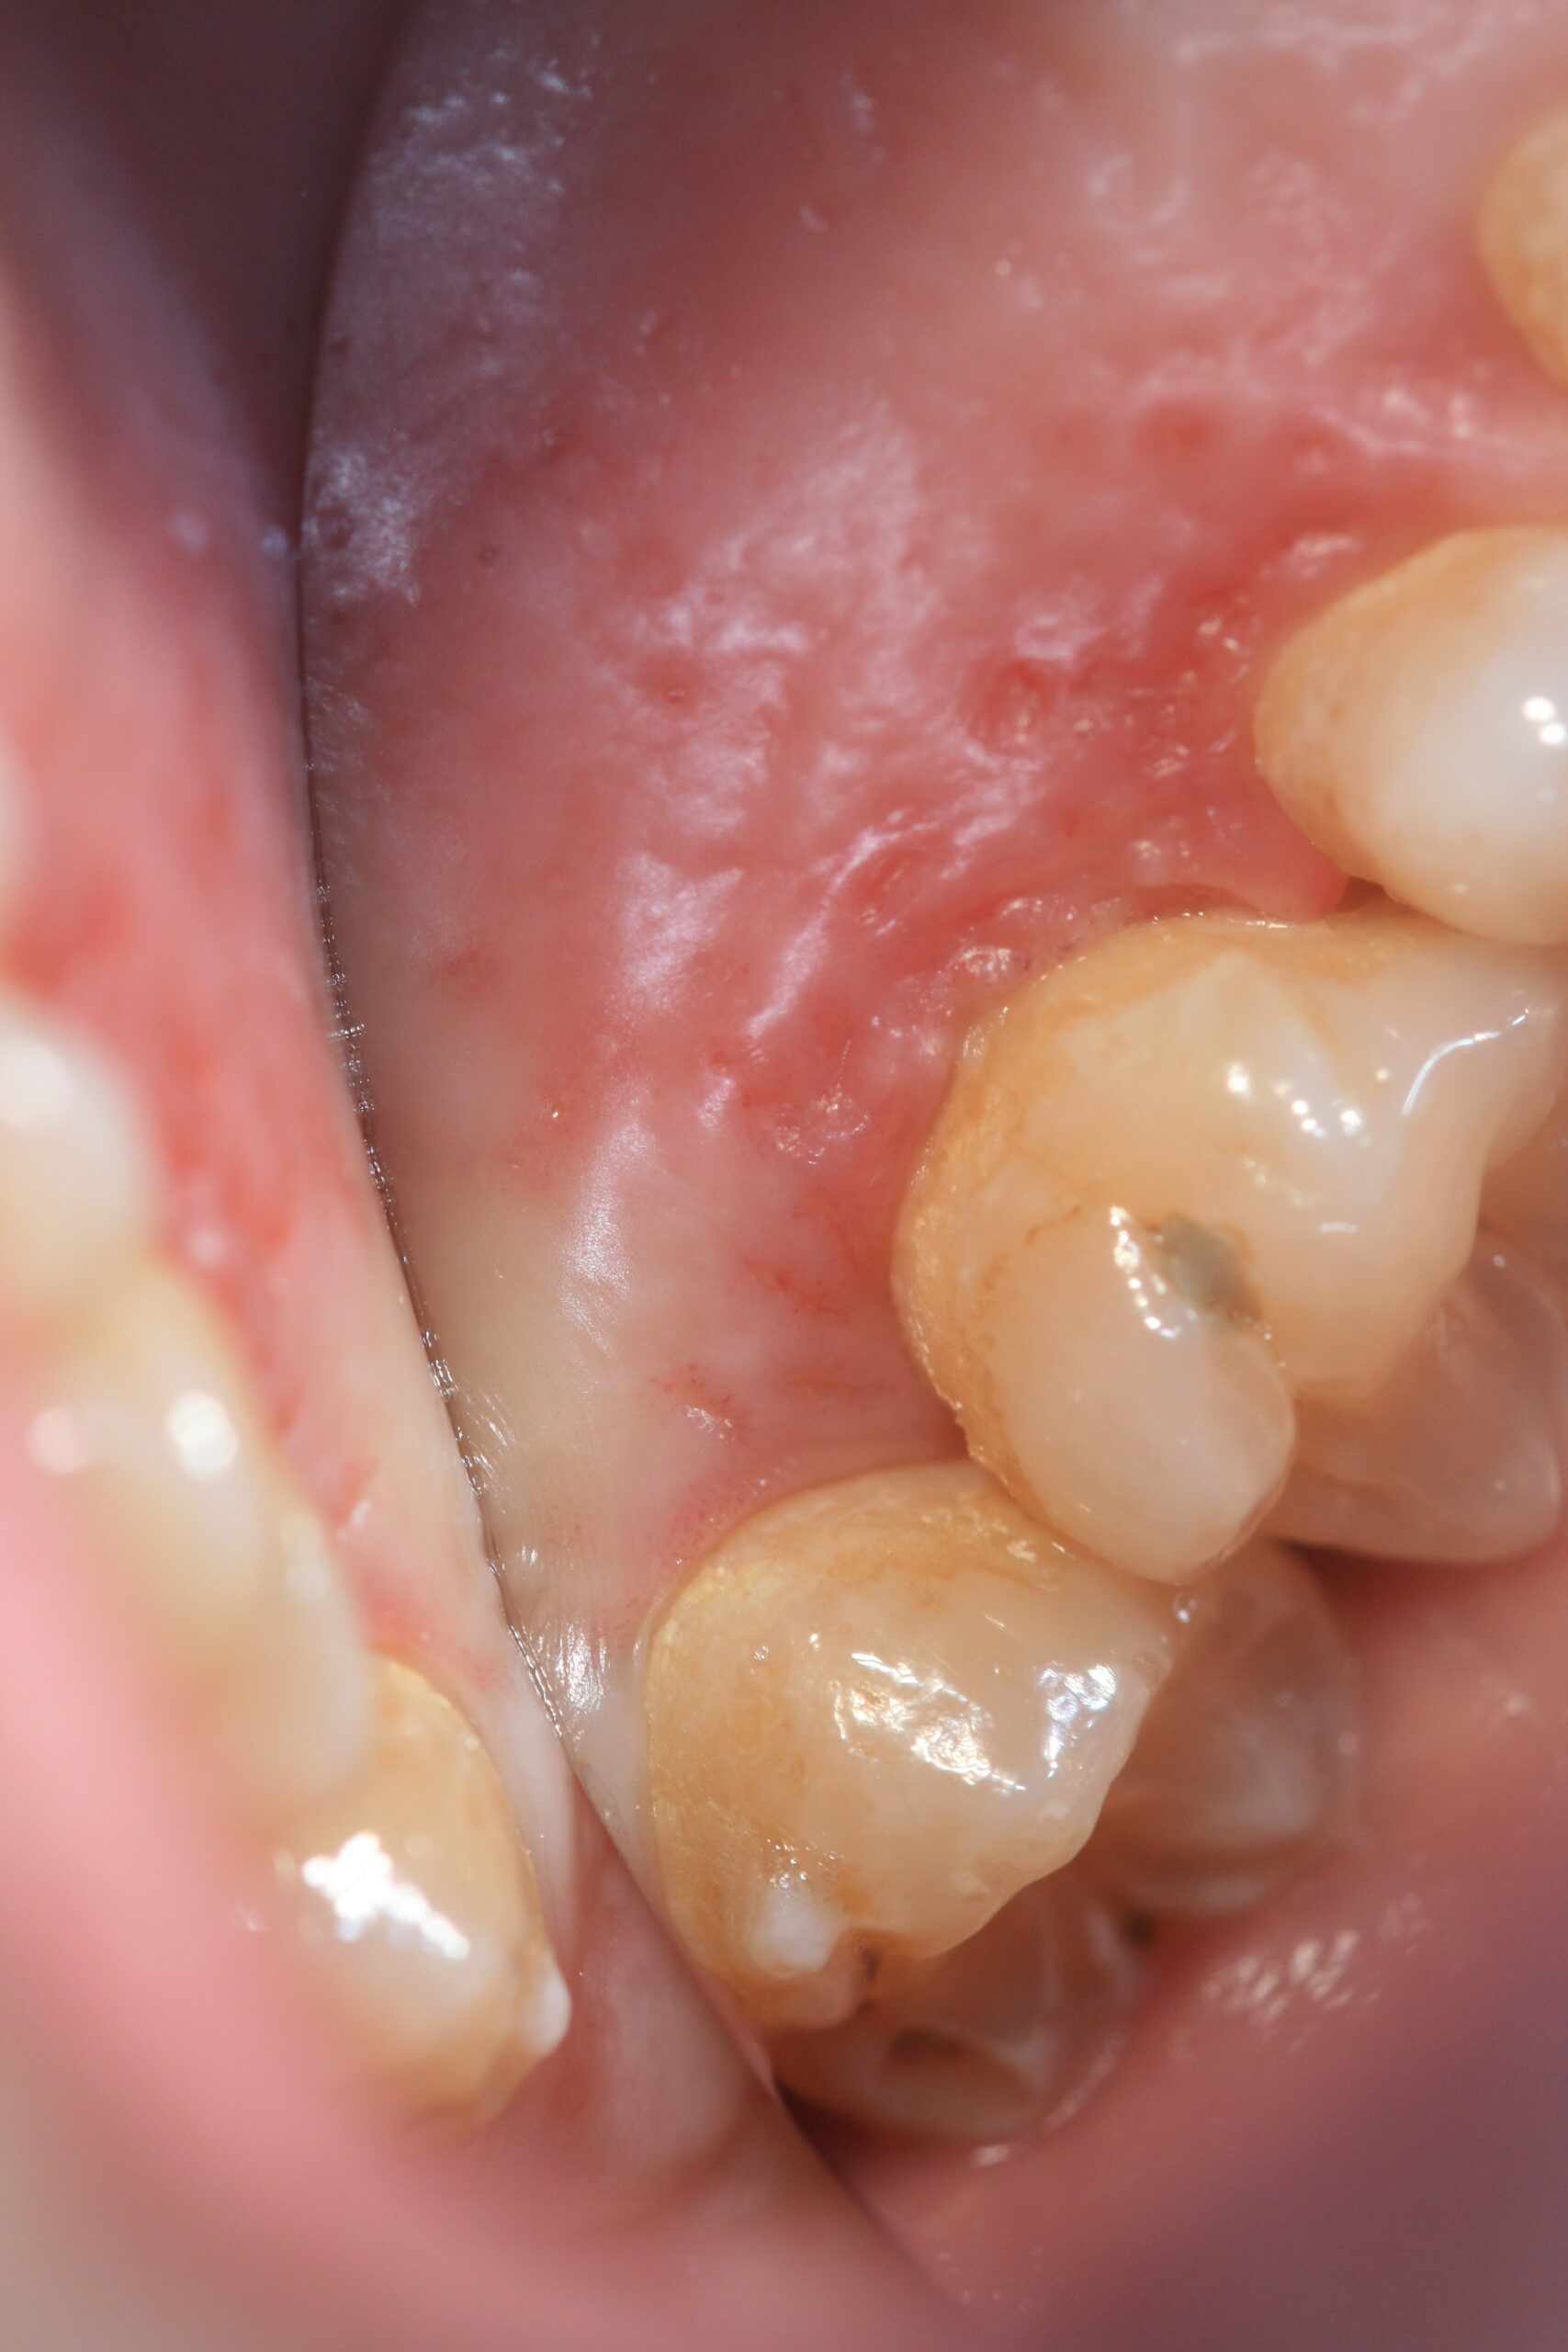

Die Zahnfleisch- und Schleimhautentzündung ist das häufigste Krankheitsbild unter der eine mit Herpes-simplex-Virus 1 erstmalig in Erscheinung tritt. Es zeigen sich viele zerstreut-verteilte Bläschen an der Mundschleimhaut, die sich in runde bis ovale, schmierig belegte Herpes-Aphten umwandeln, die sich aus den Bläschen gemeinsam entwickeln und eine erhebliche Größe entwickeln können.

Der Herpes labialis ist die bekannteste Form der HSV-Reaktivierung, also als wiederkehrender Lippenherpes, und zeigt sich als typische Herpesbläschen („cold sores“, Fieberbläschen) an der Lippenrotgrenze bis hin zum Nasenbereich, seltener auch in Form von gruppierten Schleimhautgeschwüren des harten Gaumens.